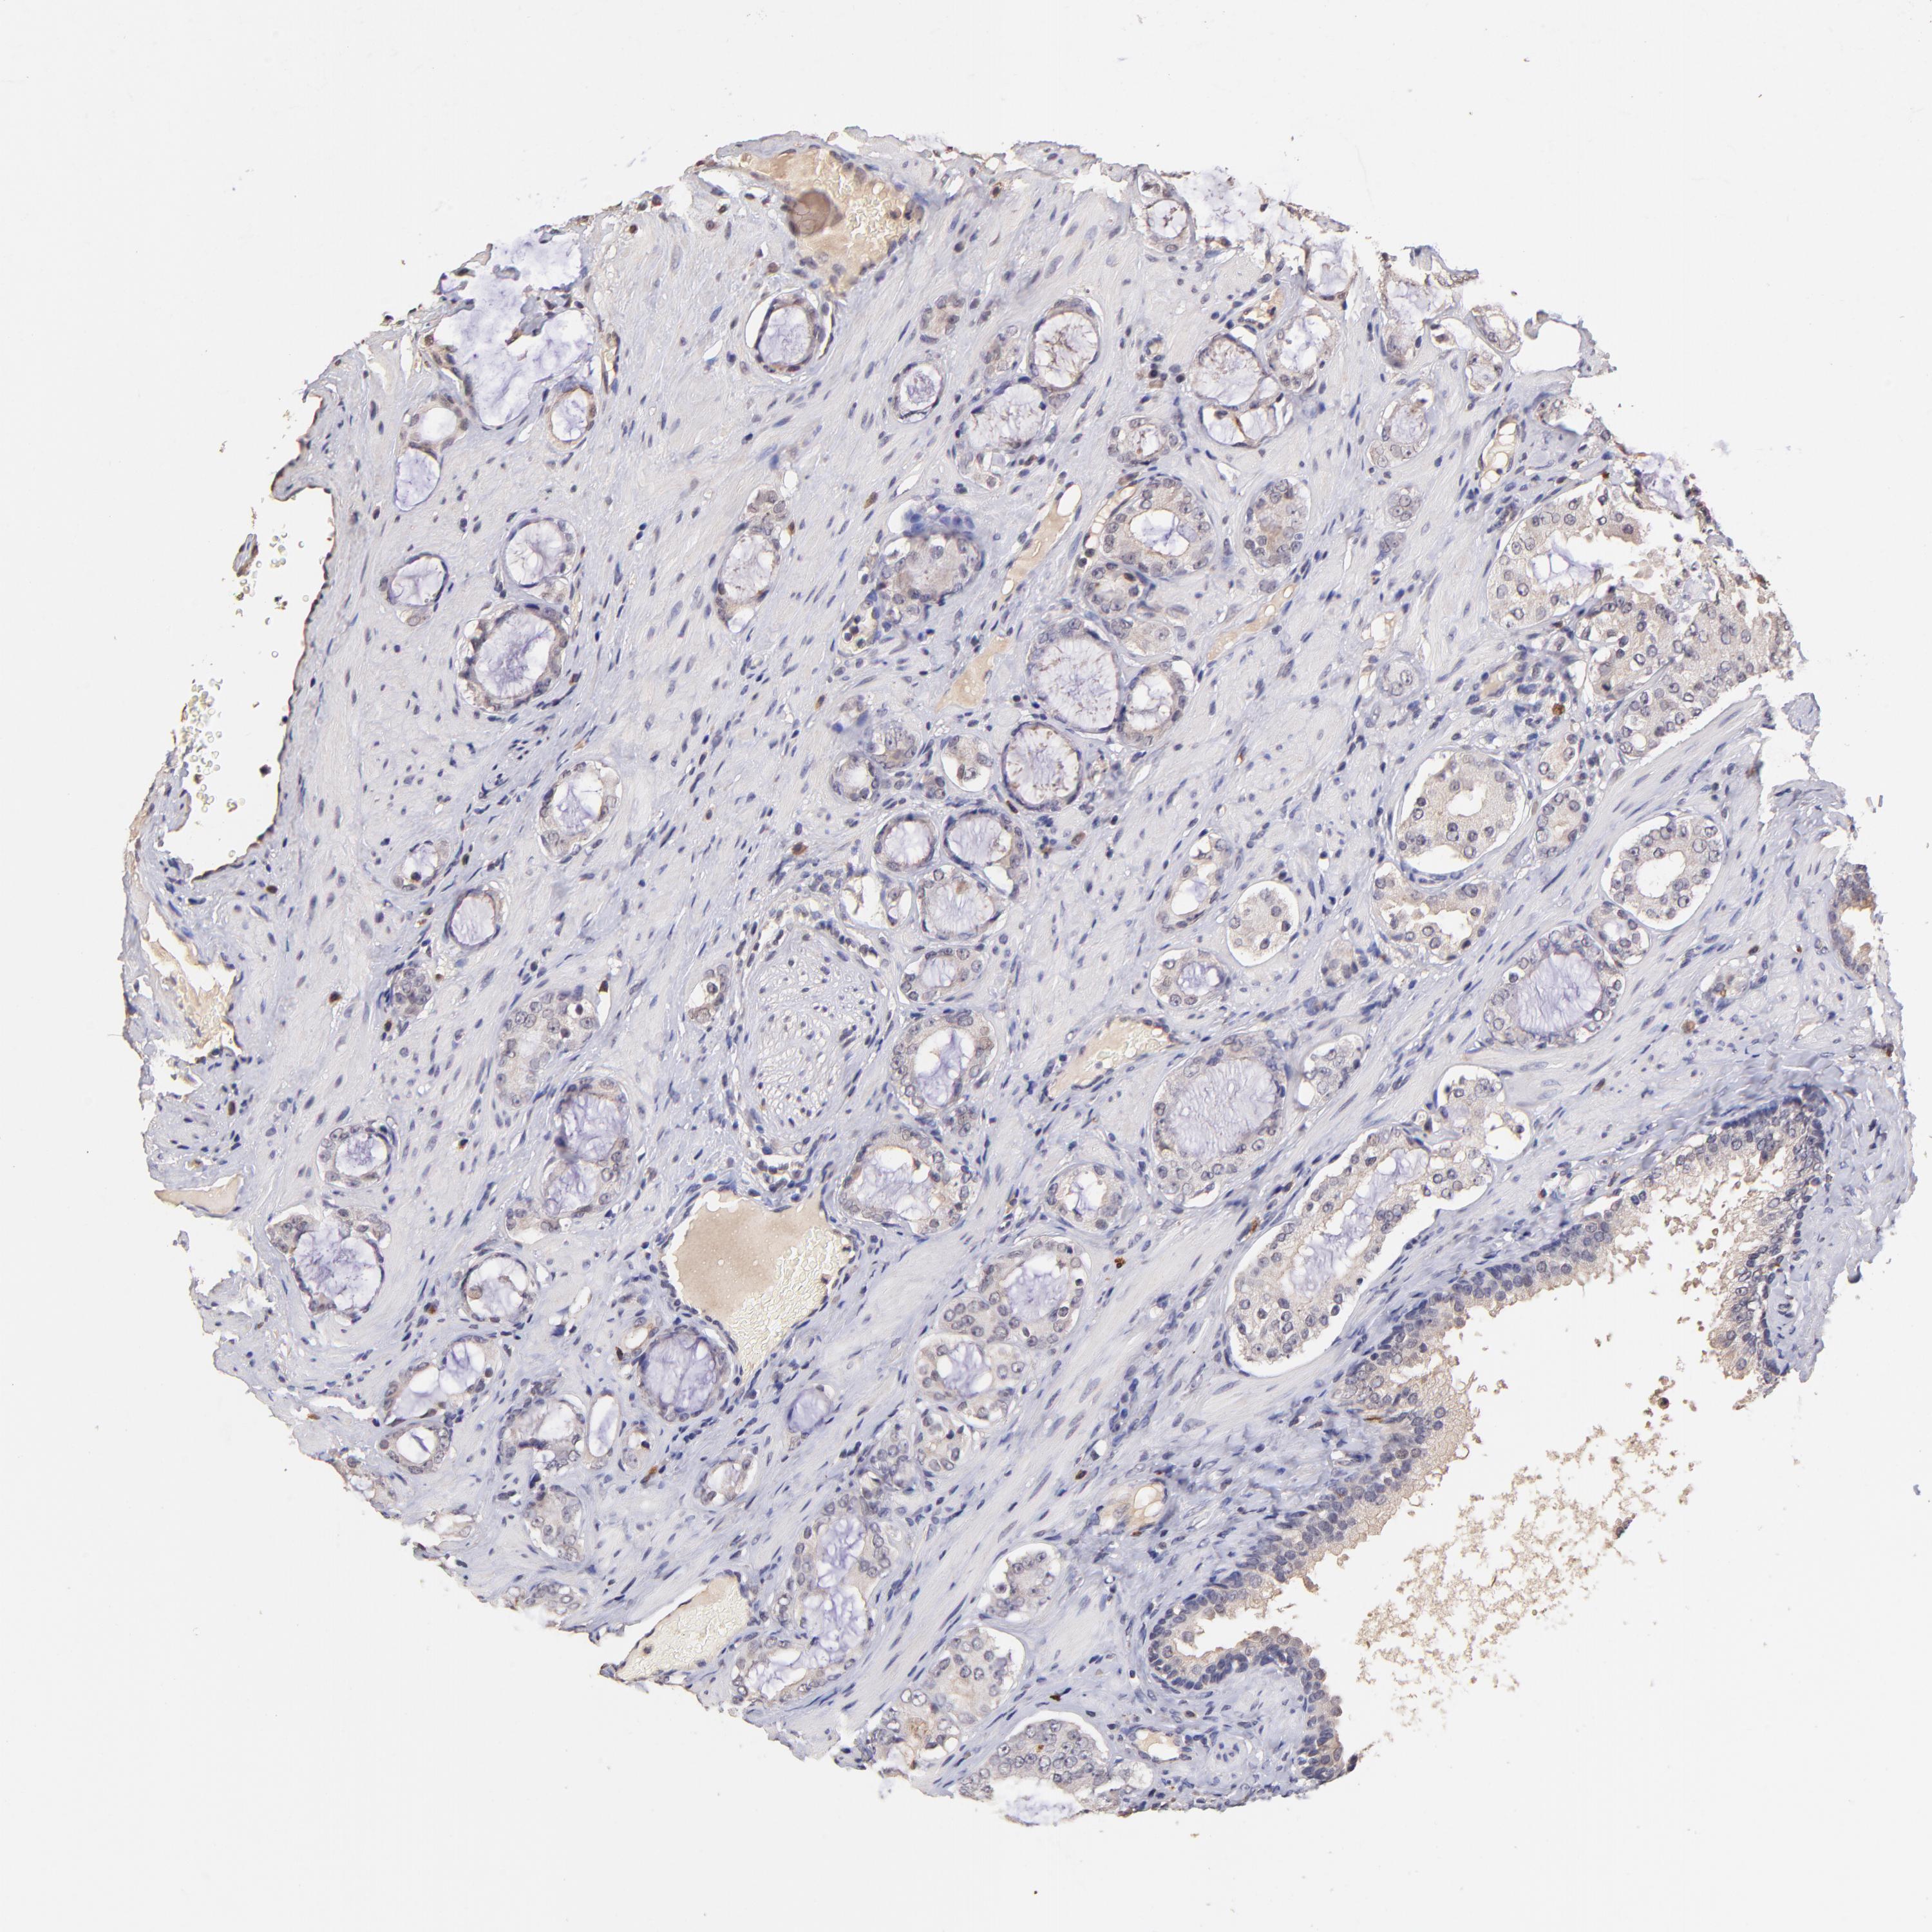

PROSTATE CANCER - Protein expressioni

A mouse-over function shows sample information and annotation data. Click on an image to view it in a full screen mode. Samples can be filtered based on level of antibody staining by selecting one or several of the following categories: high, medium, low and not detected. The assay and annotation is described here.

Antibody stainingi

Antibody staining in the annotated cell types in the current human tissue is reported as not detected, low, medium, or high, based on conventional immunohistochemistry profiling in selected tissues. This score is based on the combination of the staining intensity and fraction of stained cells.

Each image is clickable and will lead to virtual microscopy that enables deeper exploration of all samples and also displays staining intensity scores, fraction scores and subcellular localization as well as patient and tissue information for each sample.

Antibody HPA002633

Antibody HPA046758

Antibody CAB010906

Staining

High

Medium

Low

Not detected

Intensity

Strong

Moderate

Weak

Negative

Quantity

>75%

75%-25%

<25%

None

Location

Nuclear

Cytoplasmic/membranous

Cytoplasmic/membranous,nuclear

Adenocarcinoma, Medium grade

Adenocarcinoma, High grade

Adenocarcinoma, Low grade

Adenocarcinoma, NOS